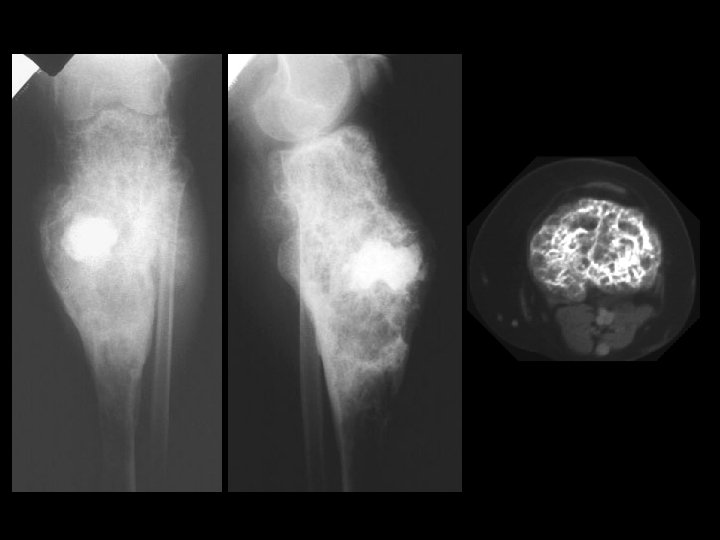

Hemangioma • Findings: – expansile lesion of the proximal tibia containing fine bony septations and a large course calcification – CT scan shows a lacey appearance • ddx: – Paget’s dz – ABC